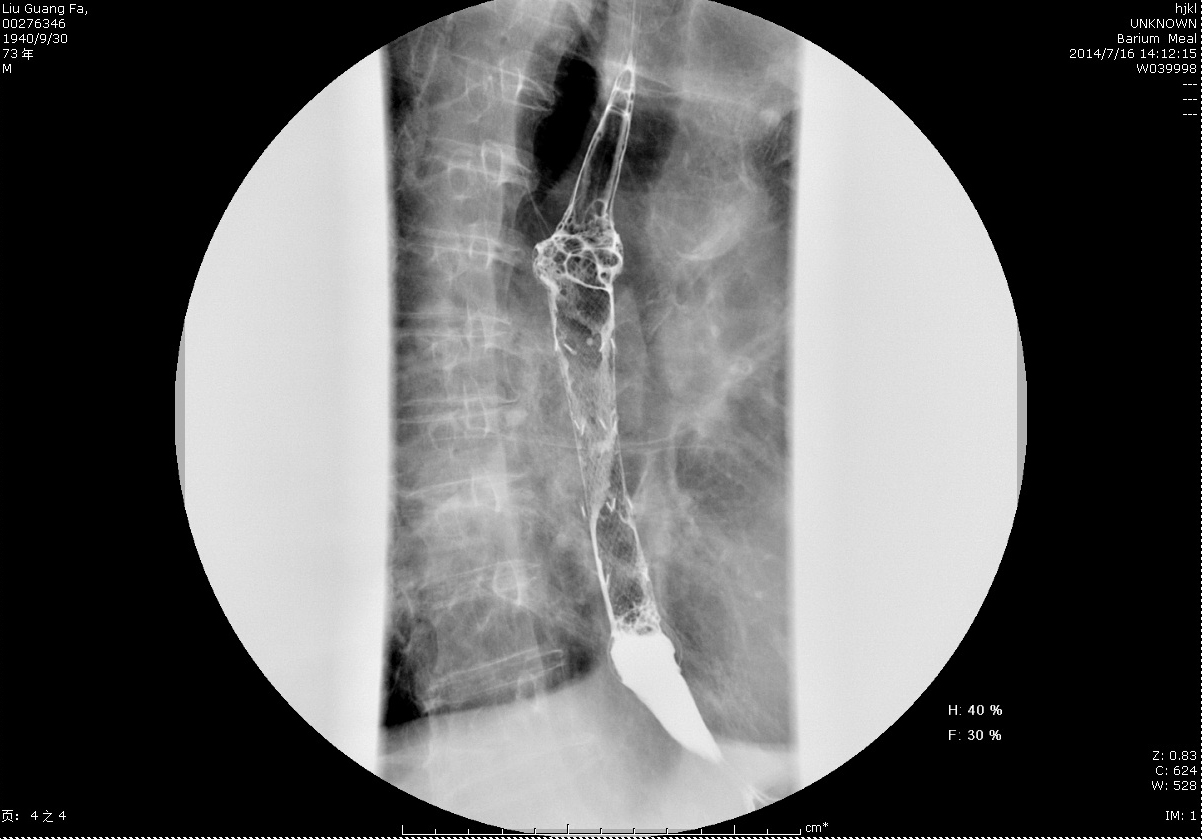

圖4+術后鋇餐